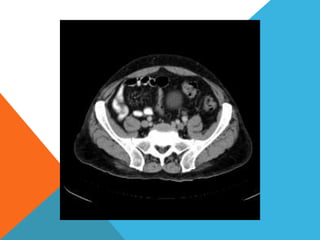

El paciente presentó síntomas de sangrado digestivo y pérdida de peso. Exámenes revelaron gastritis crónica asociada a H. pylori. Un tumor fue descubierto en una colonoscopia normal. La cirugía removió un tumor fibroide solitario, una rara neoplasia mesenquimal que usualmente crece lento y tiene bajo potencial de malignidad. El pronóstico después de la remoción quirúrgica es generalmente bueno.